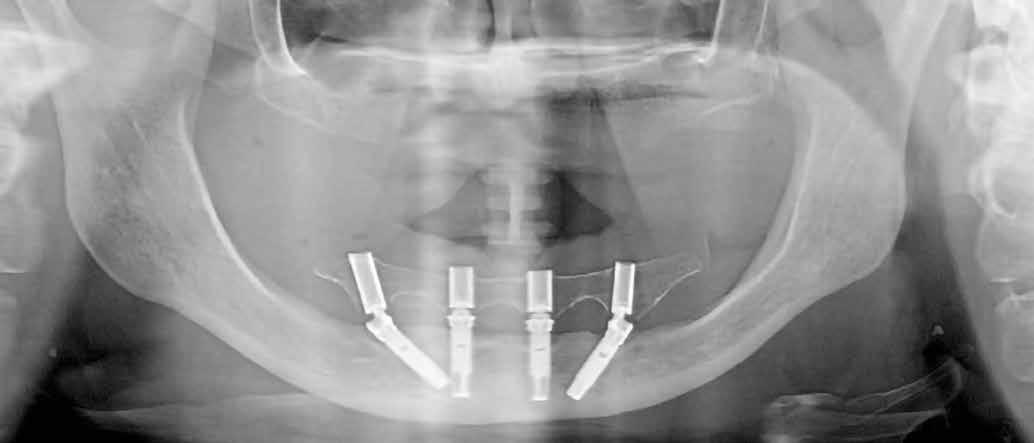

A 64 éves kaukázusi nőpáciens 2004 óta áll gondozásunk alatt, az alsó fogíven sikeres All-on-4 kezelésen van túl (1. ábra). Felső állcsontja több mint harminc éve fogatlan, de erősen motivált a sebészi rehabilitációra. A páciens elsődleges célja egy fix fogpótlás volt, amely helyreállítja a rágófunkciót és az esztétikus megjelenést (2. ábra).

Mindkét kvadránsba behelyeztünk (>50 Ncm behajtási nyomatékkal) egy-egy 5 mm átmérőjű és 42,5 mm hosszúságú implantátumot (Nobel Zygoma 0°, Nobel Biocare), a második nagyőrlők helyére (4. ábra). Az implantátumok tengelyállásának kompenzálására 45°/6 mm magasságú tengelykorrekciós multi-unit fejeket használtunk (Multi-Unit Abutment, Nobel Biocare), amelyeket 30 Ncm nyomatékkal húztunk meg [17].

A frontrégióban (1.3 és 2.1) egy-egy 3,3 mm átmérőjű és 11,5 mm hosszúságú implantátumot (Nobel Speedy Groovy, Nobel Biocare) helyeztünk be, szintén >50 Ncm behajtási nyomatékkal, amelyekre 3 mm (1.3 helye) és 2 mm (2.1 helye) magas multi-unit fejek (Multi-Unit Abutment, Nobel Biocare) kerültek, 25 Ncm nyomatékkal meghúzva (5. ábra). A lebenyeket visszafektettük, majd a műtéti területet varrattal zártuk (4/0 selyem; B. Braun Medical; 6. ábra).

A műtétet követő tizedik napon a varratokat eltávolítottuk, zavartalan sebgyógyulást tapasztaltunk. A pácienssel kontrollidőpontokat egyeztettünk kettő, négy és hat hónapos visszahívási ütemezésben (9. ábra)

Jelen klinikai eset szemlélteti egy súlyosan atrofiás maxilla rögzített fogpótlással történő rehabilitációjának rövid távú eredményeit, amely során két extramaxillarisan beültetett zygoma implantátumon és 45 fokos tengelykorrekciós fejen, és két hagyományos implantátumon került elhorgonyzásra egy azonnal funkcióba helyezett fix fogpótlás. A protetikai munka, az implantátumok és a fejek sikeraránya is magasnak bizonyult. Ez az eljárás számos előnnyel rendelkezik az egyéb terápiás lehetőségekkel, név szerint a csontaugmentációval szemben: kiszámíthatóbb, egyszerűbb, magasabb a sikerarány, nagyobb a páciens komfortérzete, esztétikusabb a végeredmény és azonnal biztosítható egy alacsony bekerülési költségű, ideiglenes fogpótlás [6, 18, 19]. Az extramaxillaris All-on-4 hibrid eljárás legnagyobb előnye például a csípőlapátból történő csontátültetéssel szemben a magasabb sikerarány. Az extra hosszú implantátumok maxillába, illetve zygomába való extramaxillaris behelyezése lehetővé teszi az anatómiai korlátok leküzdését és új lehetőségeket nyit a rögzített implantációs fogpótlások készítésére, extrém körülmények között.

9. ábra: Posztoperatív panorámaröntgen.